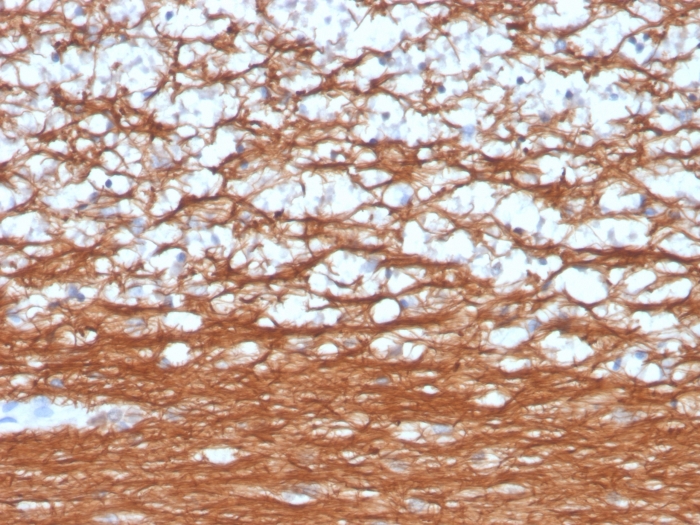

Formalin-fixed, paraffin-embedded human cerebellum stained with Pgp9.5 Mouse Recombinant Monoclonal Antibody (rUCHL1/4557).

This MAb reacts with a protein of 20-30kDa, identified as PGP9.5, also known as ubiquitin carboxyl-terminal hydrolase-1 (UchL1). Initially, PGP9.5 expression in normal tissues was reported in neurons and neuroendocrine cells but later it was found in distal renal tubular epithelium, spermatogonia, Leydig cells, oocytes, melanocytes, prostatic secretory epithelium, ejaculatory duct cells, epididymis, mammary epithelial cells, Merkel cells, and dermal fibroblasts. Furthermore, immunostaining for PGP9.5 has been shown in a wide variety of mesenchymal neoplasms as well. A mutation in PGP9.5 gene is believed to cause a form of Parkinson’s disease.